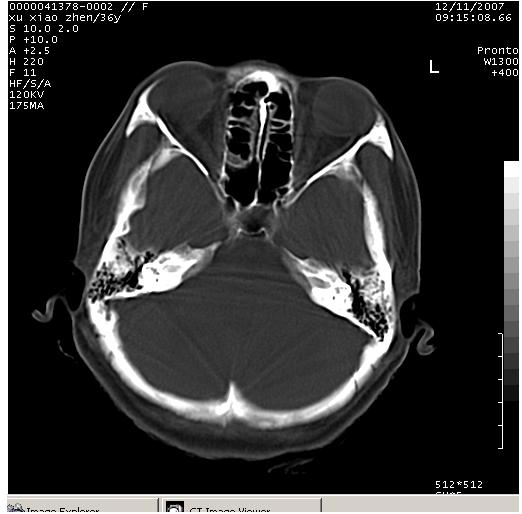

以下是引用wzr在2007-12-12 18:58:00的发言:[br]以脑白质受累,脑肿胀明显,脑室变窄,多考虑炎性改变,建议进一步ce或mri明确.

以下是引用wqs571018在2007-12-12 19:48:00的发言:[br]脑白质受累,脑肿胀明显,脑室变窄,多考虑炎性改变,脑膜炎可能性大;建议mri明确.。